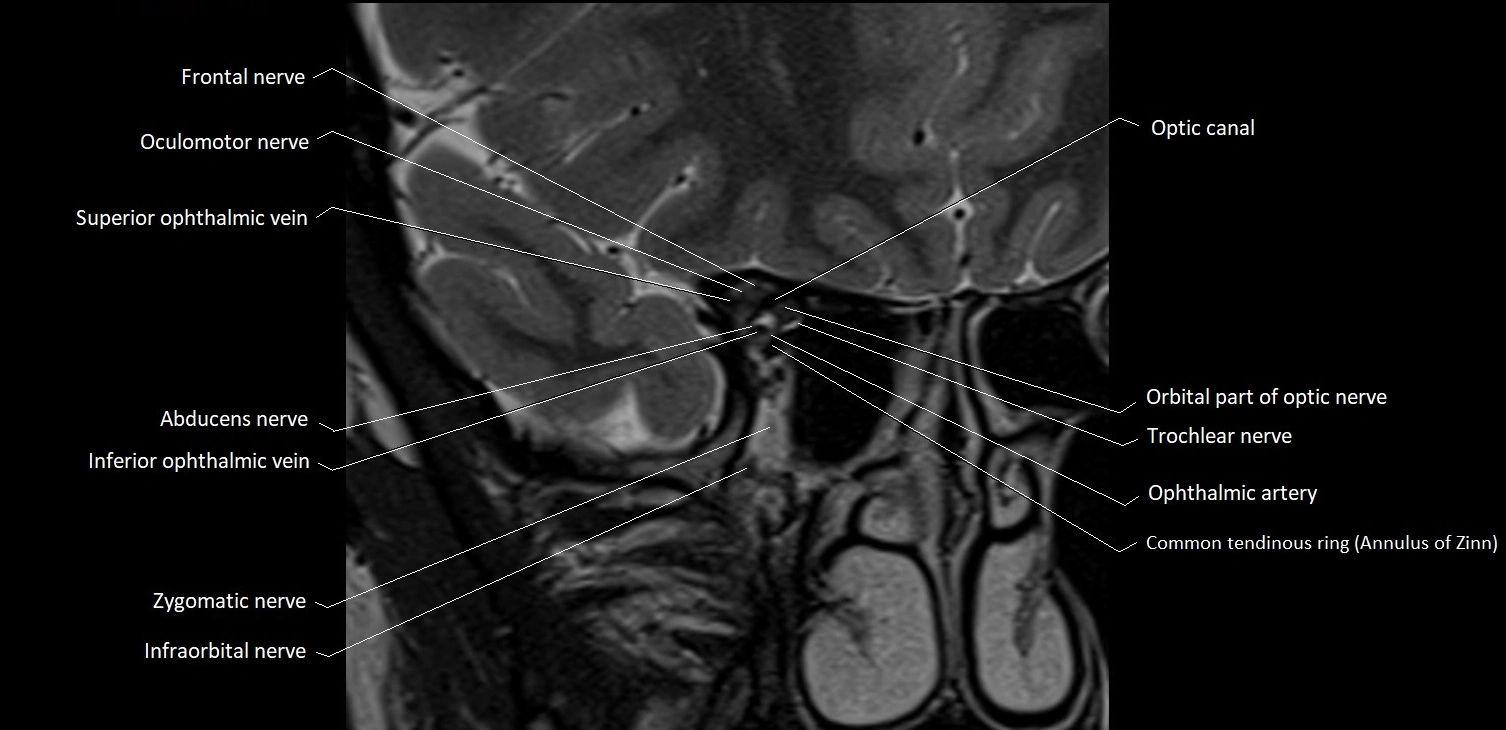

- Abducens nerve (Cranial nerve VI)

- Common tendinous ring (Annulus of zinn)

- Frontal nerve

- Inferior ophthalmic vein

- Infraorbital nerve

- Oculomotor Nerve (Cranial Nerve III)

- Optic canal

- Orbital part of optic nerve

- Superior ophthalmic vein

- Trochlear nerve (Cranial nerve IV)

- Zygomatic nerve